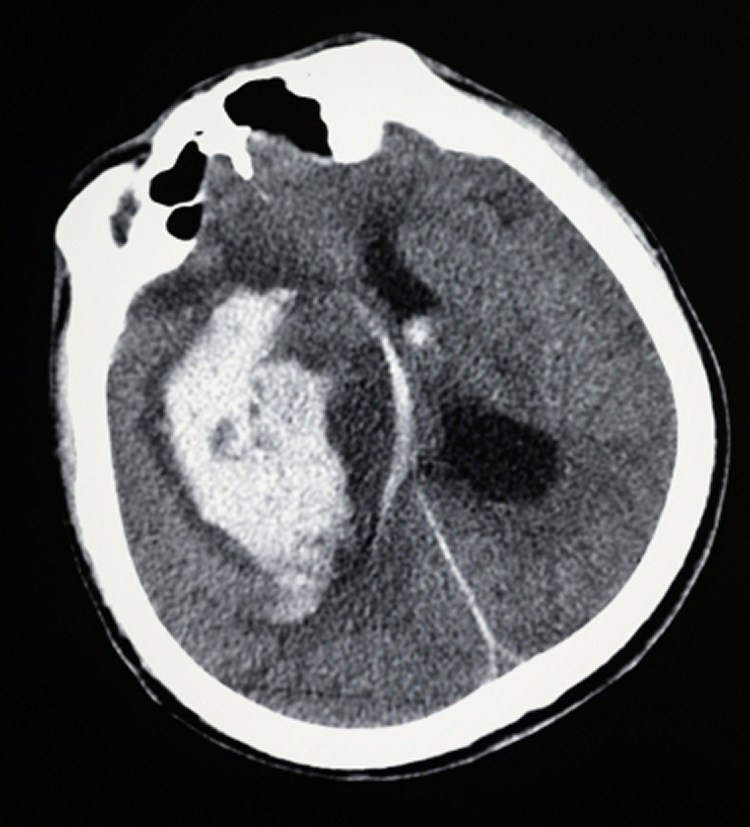

Менингиома на голове КТ NeuroscienceNews.com изображение зачисляется в UCSF.